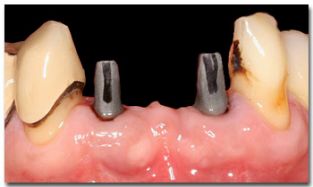

Een brug op implantaten

In dit geval ontbreken meerdere gebitselementen. Om een niet uitneembare en dus vaste vervanging te maken zijn in dit geval twee implantaten geplaatst, waarover heen een vier-delige brug is vastgelijmd. Het is niet altijd nodig om voor elk ontbrekend gebitselement een implantaat te plaatsen; bijvoorbeeld een drie-delige brug kan soms bijvoorbeeld ook op twee of op drie implantaten geplaatst worden, de behandelend tandarts-implantoloog kan dit in uw individuele situatie beoordelen.